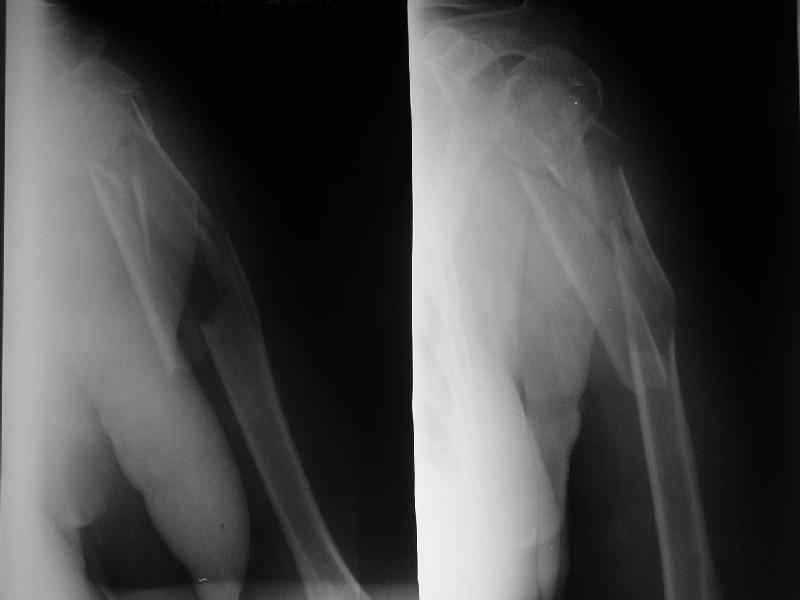

Доминирующая ли рука и какая профессия?

Если выбор на интрамедулярный штифт, я бы сделал КТ головки, информация необходима для определения вовлечения головки в перелом, имеется опасность

расколочения и для ориентира расположения блокирующих шурупов.

Другой вариант, небольшой гипс на локтевой сустав как груз для тракции, повязкой за кисть выше-вниз можно контролировать сгибание и разгибание на место перелома, небольшая отводящая подушка в живот (у женщин молочная железа в зоне перелома

создает варус)сделать ренген снимки через одну недели. Перелом низкоэнергетический, может быть, без операции обойдется.

"Рука не доминирующая, но тоже нужна" - А.Н. Челноков. Больная уже лечилась консервативно в гипсовой повязке и на вытяжении, в настоящее время настаивает на оперативном лечении.

Есть и другие косые снимки, на которых не определяется вовлечение головки, если успеем - сделаем КТ. Спасибо за интерес к нашему случаю.

Ув. коллеги. Интересно, насколько разрушена головка, особенно ее артикулирующая поверхность, может для начала сделать КТ головки.

На счет операции - стоит ли ее вообще делать, куда Вы собираетесь забить стержень, на расколете ли головку, если она еще целая. В любом случае Вы

не добъетесь стабильной фиксации, прийдеться иммобилизировать где-то на месяц. Вопрос: какова будет функция после травматичной операции, а она

имеенно таковой будет и последующей иммобилизации. ВЧКДО сделать не получиться - не за что зацепиться.

> Ув. коллеги. Интересно, насколько разрушена головка, особенно ее

> артикулирующая поверхность, может для начала сделать КТ головки.

По нескольким снимкам в чуть разых проекциях она не фрагментирована. А если и были трещины, за прошедшие 3 недели они "слиплись", очевидно. А КТ если сделаем - еще можем испугаться увиденного :-)